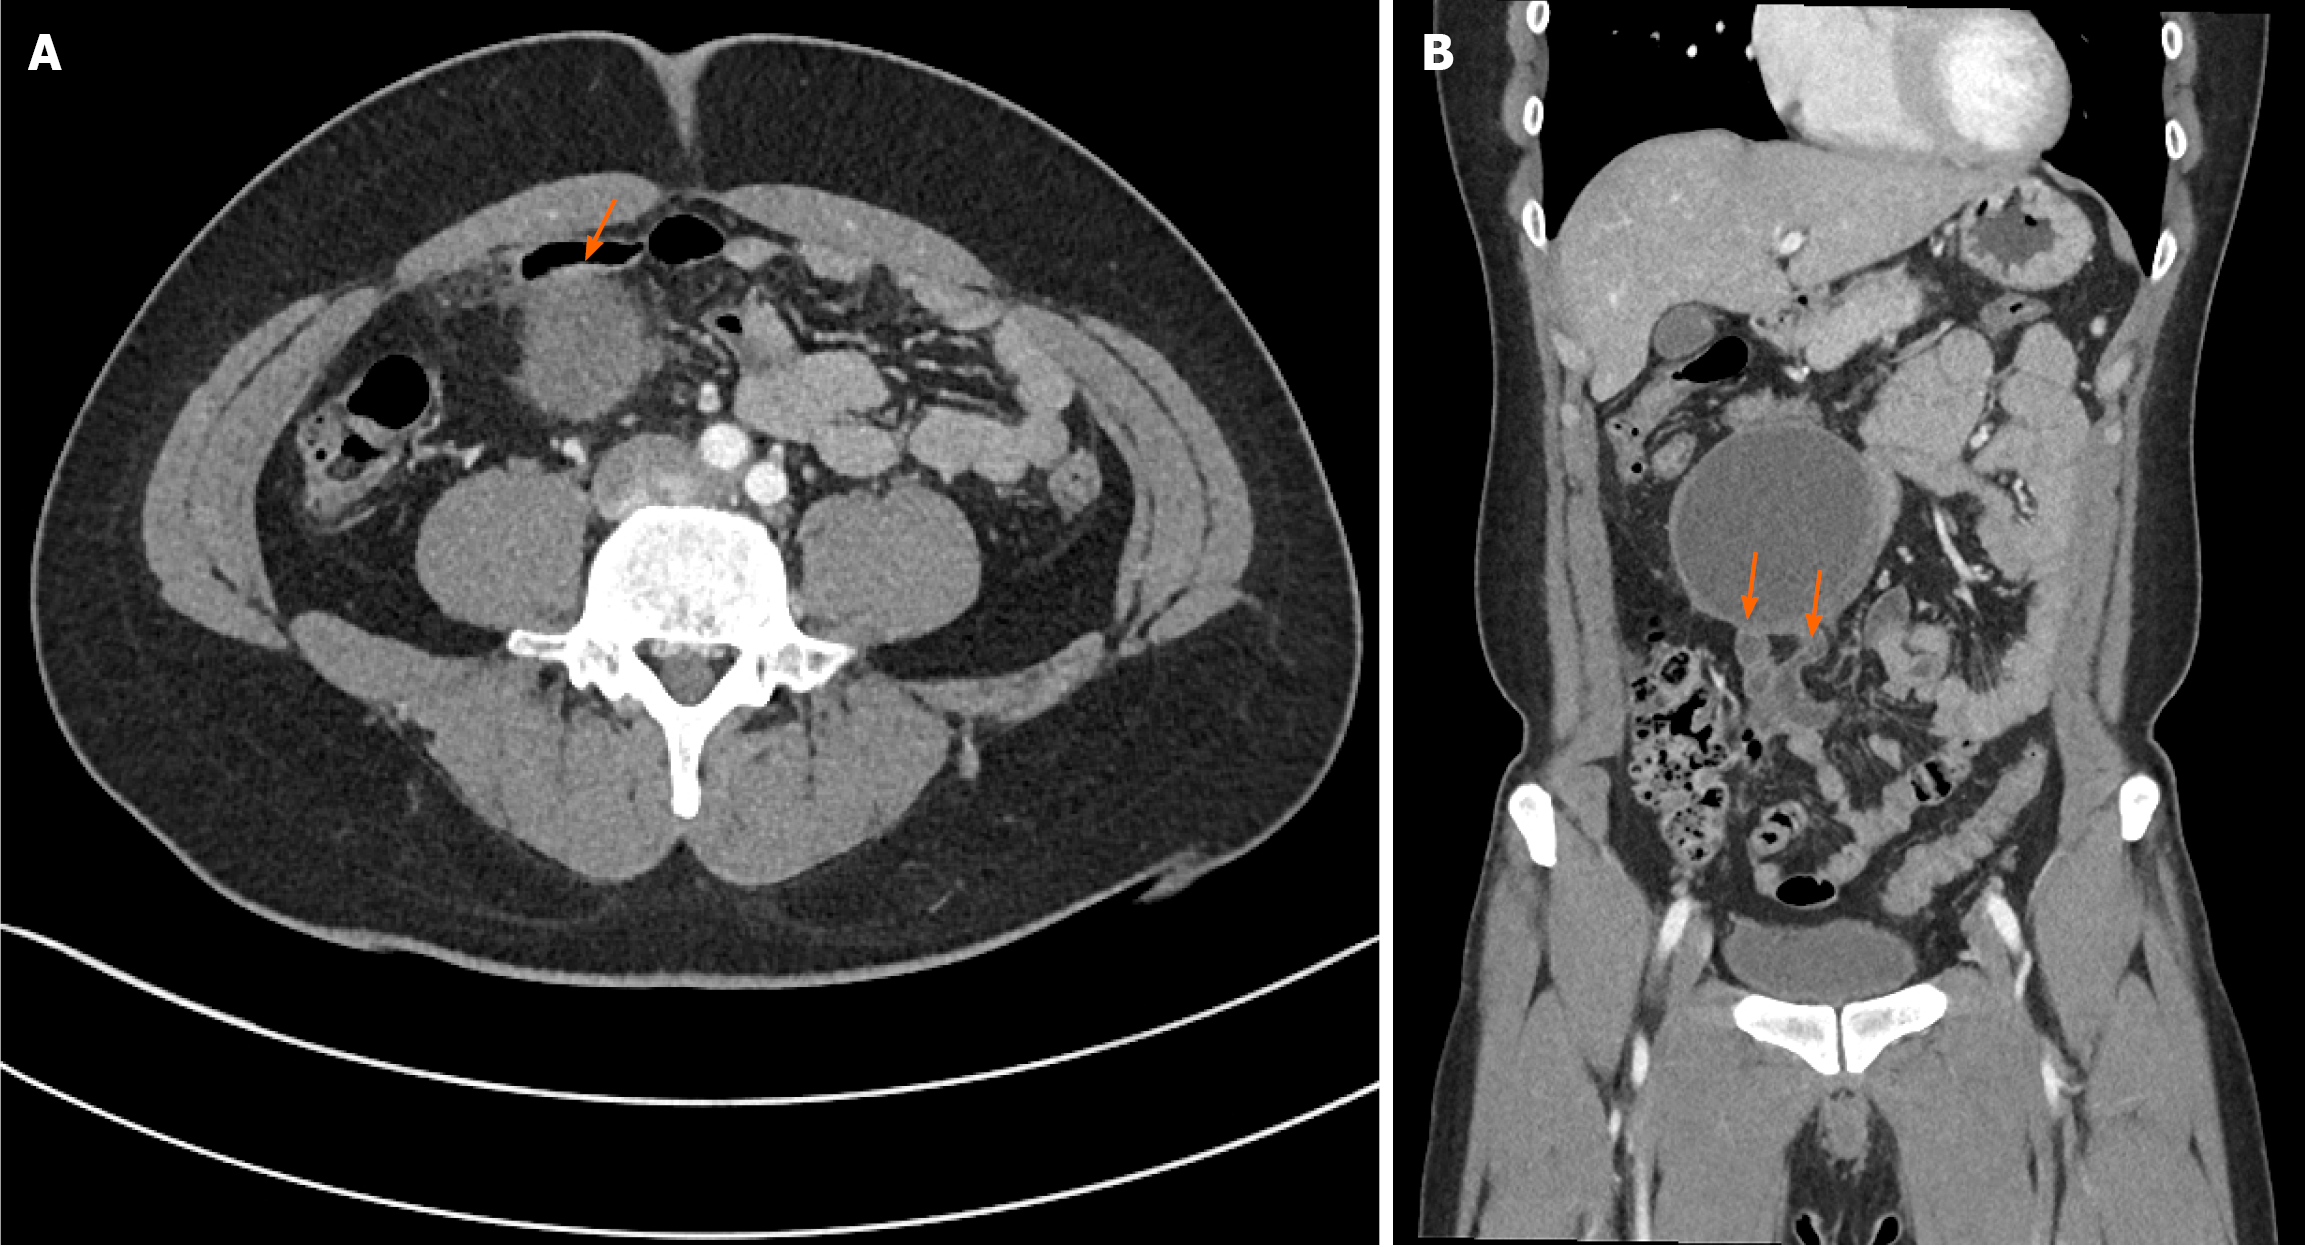

An abdominal contrast-enhanced CT revealed a well-circumscribed mass of approximately 10 cm located in the small bowel mesentery (Figure 1). The lesion demonstrated markedly low attenuation in the central portion with a solid, enhancing peripheral rim, creating a radiological appearance highly suggestive of a GIST. The mass was tightly abutting adjacent ileal loops, raising suspicion of a mural or mesenteric origin. There were no associated liver lesions, ascites, or lymphadenopathy, and no other abnormal intra-abdominal findings were identified.

| Diagnostic evaluation | Contrast-enhanced abdominal CT | Well-circumscribed mass with central low attenuation and peripheral enhancement, strongly suggestive of a GIST |